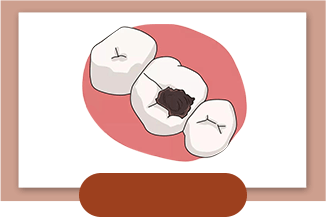

牙蛀牙/龋齿

牙疼不是病 小心蛀牙把你的钱包掏空!

小心蛀牙把你的钱包掏空!

轻微蛀牙如果不及时补上

小心蛀牙把你的钱包掏空!

小心蛀牙把你的钱包掏空!

轻微蛀牙如果不及时补上 会引起一系列并发症

严重的会导致牙齿脱落

浅龋

Level 1 - 疼痛指数:★

- 烧钱指数:★

- 浅阶段痛感低,易治疗,花费也相对少

- 治疗方法:树脂补牙(过程简单快速,不痛苦)

- 到院次数:1次

- 治疗时间:约30分钟/次

中龋

Level 2 - 疼痛指数:★★

- 烧钱指数:★★

- 此时牙本质已经受到侵害,无法依靠树脂补牙填补牙洞。

- 治疗方法:嵌体补牙(相对更牢固)

- 到院次数::2-3次

- 治疗时间:30分钟/次

深龋

Level 3 - 疼痛指数:★★★

- 烧钱指数:★★★

- 牙本质深层咬东西感到刺痛,伤及牙神经,此时须进行根管治疗才能拯救你的牙。

- 治疗方法:根管治疗(守住天然牙的最后防线)

- 到院次数:2-3次

- 治疗时间: 1小时/次

牙髓炎

Level4 - 疼痛指数:★★★★★(治疗时会打麻药)

- 烧钱指数:★★★★★

- 若错过根管治疗,齲齿发展到无法拯救的地步,只能进行拔除操作。

- 治疗方法:全瓷牙/种植牙(缺失牙修复的理想选择)

- 到院次数:多次就诊

- 治疗时间:视情况而定